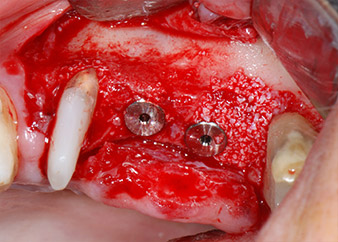

Implant beds were prepared at sites 25 and 26 with rotary instruments, used in a contra-angle handpiece with a 20 : 1 transmission ratio with an updated powerful implant motor (Implantmed, W&H) (Fig. 8).

The implants (Restore, Keystone Dental, diameter 3,75 mm, length 8.0 mm) were placed with the implant motor

(Figs. 11 and 12).